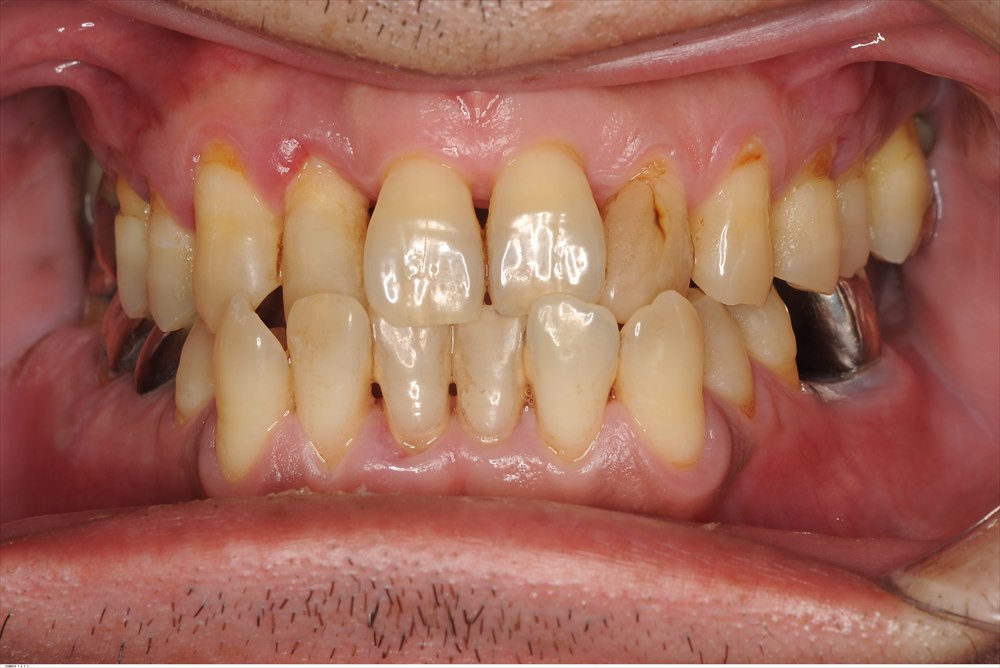

症例を1つ

右上の二番目の前歯(腫れている歯)こちらはポケットが12mmあり、骨が根尖付近までなくなっています。